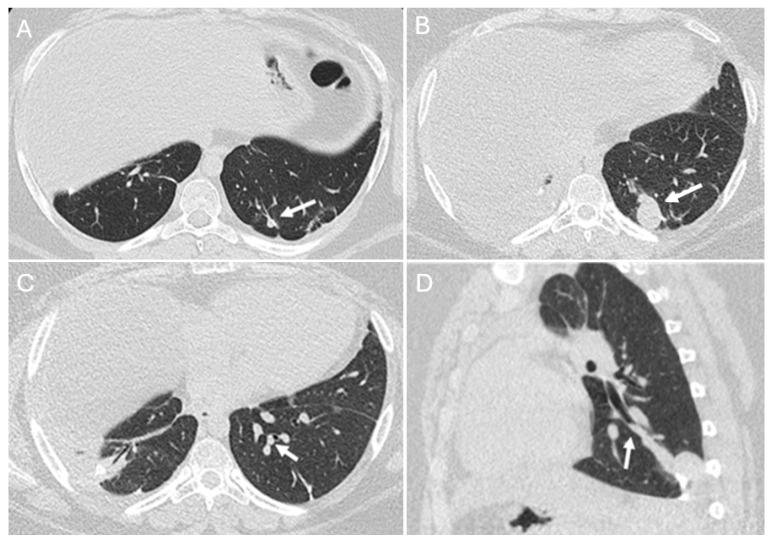

Osteosarcoma, a primary bone malignancy in children and adolescents, frequently metastasizes to the lungs, contributing significantly to morbidity and mortality. At diagnosis, 15-20% of patients present with detectable lung metastases. Chest computed tomography (CT) is vital for the early detection and monitoring of these metastases. Lung involvement typically presents as multiple nodules of varying sizes and can include atypical features such as cavitation, cystic lesions, ground-glass halos, intravascular tumor thrombi, and endobronchial disease. Pleural metastasis often occurs alongside pulmonary disease, and complications like spontaneous pneumothorax may arise. Additional findings may include thoracic lymphadenopathy, cardiac tumor thrombus, and chest wall deposits. Familiarity with these imaging patterns is essential for radiologists to ensure timely diagnosis and effective management. This review highlights the critical role of chest CT in detecting and characterizing osteosarcoma metastasis.

骨肉瘤是儿童和青少年常见的原发性骨恶性肿瘤,常转移至肺部,对发病率和死亡率有显著影响。在诊断时,15%至20%的患者出现可检测到的肺转移。胸部计算机断层扫描(CT)对于这些转移灶的早期检测和监测至关重要。肺部受累通常表现为大小不一的多个结节,可包括一些非典型特征,如空洞形成、囊性病变、磨玻璃晕、血管内肿瘤血栓和支气管内病变。胸膜转移常与肺部疾病同时发生,可能出现自发性气胸等并发症。其他表现可能包括胸内淋巴结肿大、心脏肿瘤血栓和胸壁转移灶。放射科医生熟悉这些影像学表现对于确保及时诊断和有效治疗至关重要。本综述强调了胸部CT在检测和鉴别骨肉瘤转移方面的关键作用。